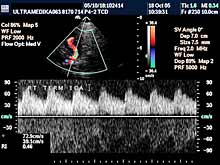

- transkranijalni kolor Doppler (TCD) i 3D CPA pregled

(otkrivanje

kritičnih stenoza, i proširenja-aneurizmi krvnih sudova mozga),

Primenjene tehnike:

- Broadband-CD,

- CPA,

- CPD,

- 3D CPD,

- Sono CT,

- XRes,

- 2D Broadband.